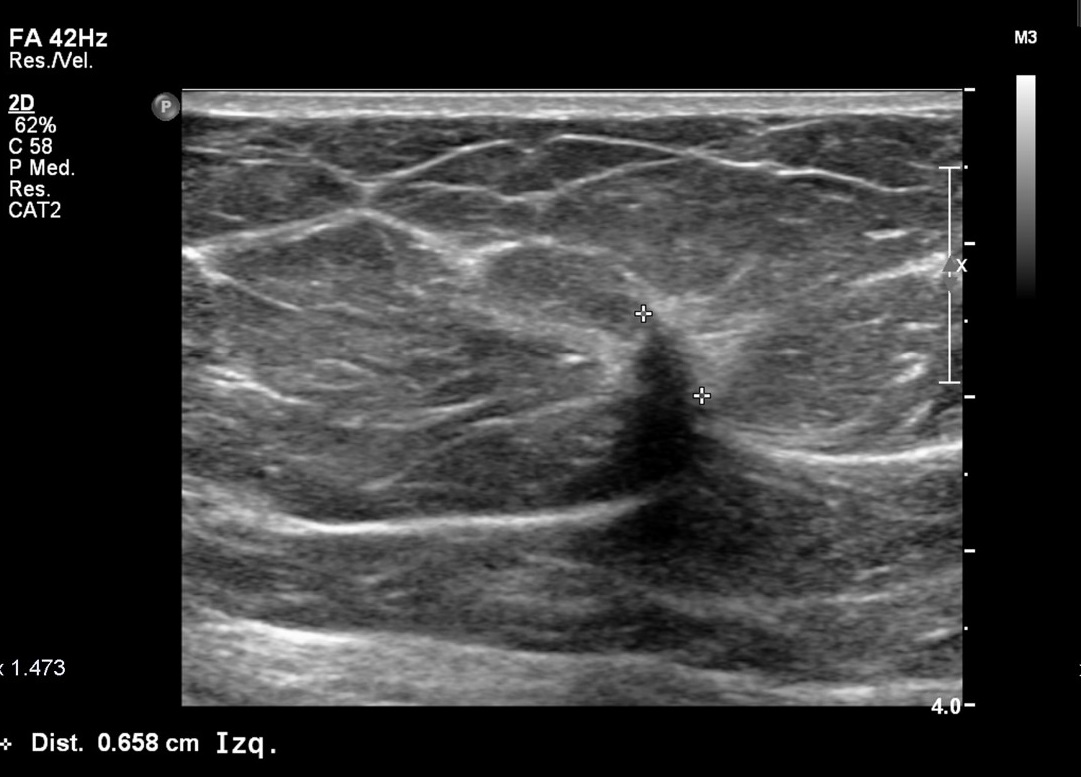

Caso 29

La ecografía es la técnica complementaria ideal de la mamografía pues nos permite distinguir si una lesión es de contenido líquido o de contenido sólido (esto disminuye el número de biopsias innecesarias). Además, también nos permite medir el tamaño de la lesión, algo que no se puede hacer en la mamografía, y no conlleva radiación para el paciente. Destacar que también debería realizarse una BAG pues se trata de una BIRADS 4c.